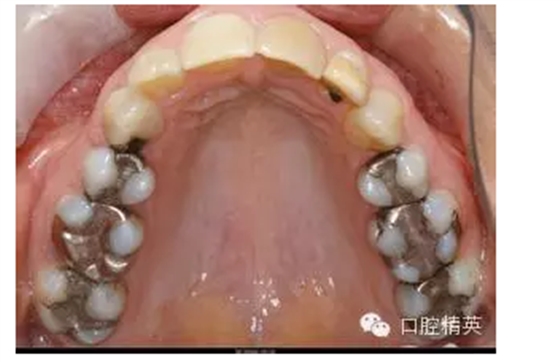

現(xiàn)在主要有兩種材料:銀汞合金和樹脂。銀汞合金補(bǔ)一顆牙100-300塊錢,樹脂則要100-800不等,相差還是蠻懸殊的。

銀汞合金可以說是歷史最為悠久的補(bǔ)牙材料之一,極其經(jīng)典,應(yīng)用了一百多年。主要優(yōu)點(diǎn)是硬度高、價格低廉。缺點(diǎn)是需要磨牙的量相對大,這一點(diǎn)對于很多患者來說無法忍受;另外和牙齒之間沒有粘接性,很難和牙齒緊密相接,容易脫落或繼發(fā)新的齲齒;不美觀,即使進(jìn)行了拋光處理,也只是金屬色,有的使用時間長了呈黑色,放在嘴里那是相當(dāng)?shù)拿黠@;最后一個缺點(diǎn)就是銀汞合金相對于牙齒來說太硬了一點(diǎn),以致于如果下牙補(bǔ)了一塊銀汞,與它相對的上牙會發(fā)生比較厲害的磨損,而合金巋然不動。

樹脂正是為了解決以上的種種問題而應(yīng)運(yùn)而生的新型材料,現(xiàn)在已經(jīng)非常成熟了,相關(guān)的粘接技術(shù)已經(jīng)發(fā)展到第十代了。優(yōu)點(diǎn):好看,基本和牙齒一個顏色,一個優(yōu)秀的樹脂修補(bǔ)外行應(yīng)該是看不出來痕跡的;與牙齒有粘接作用,比較密合,而且相應(yīng)的需要磨除的牙齒就要少很多了,減少病人的痛苦和臨床操作時間。硬度則恰到好處,和牙齒的物理性能比較接近,不會造成與其相對牙齒的過度磨損。另外有些比較敏感的病人如果嘴里有金屬的充填體可能會導(dǎo)致一些口腔粘膜的問題,比如苔蘚樣病變。